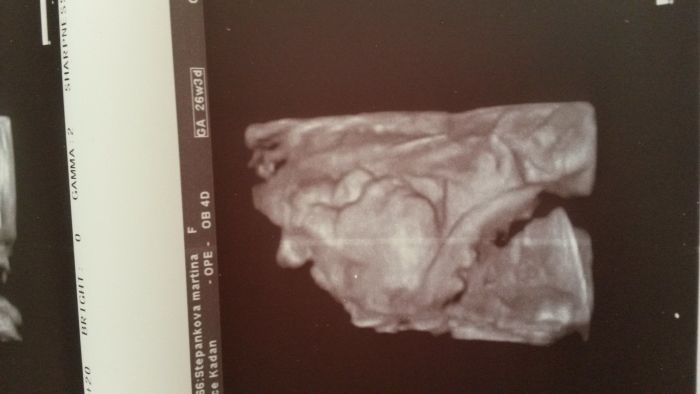

Tak ja dnes absolvovala vysetreni na tehu cukrovku. Stravila jsem tam skoro ctyri hodiny, sileny,uz jsem zase mela ty pocity řezani v podbrisku. S prvnim prckem si pamatuji ze jsem prisla,dali me to vypit a za dve hodky jsem odchazela. Ted novinka, nejdriv odber kde po skoro 1,5hod me rekli momentalni hladinu cukru,pak vypit, hned odber,za hodku znova a za dalsi hodku znova odber...sileny. ctyrikrat odber,ale to cekani v silenym vzduchu v cekarne byl teda ocistec ?. A odpo jsem se tesila na 3D ultrazvuk.obrazek a ta potvurka celou dobu k nam otocena zadama s rucickami pres oblicej, takze z toho bylo prd a zkusime to pry za 3tydny znova. ?